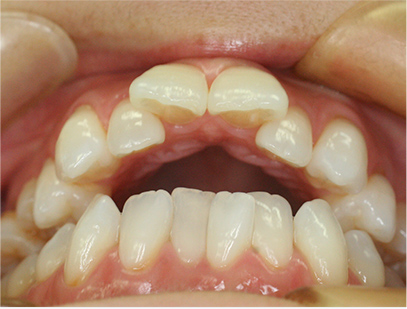

症例03

前歯が咬み合ってなく開咬の症例

上下の前歯が咬んでない事と前歯のデコボコを主訴として来院されました。

通常通り検査を行い「前歯部にデコボコを伴う開咬」と診断されました。

治療前

• 正面

• 上側

• 下側

• 右側

• 左側